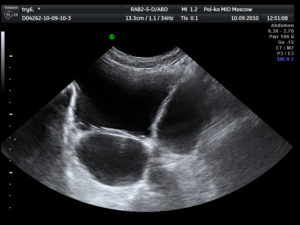

Нормальными показателями мочевого пузыря у мужчин являются:

- округлая форма с четкими и ровными контурами;

- эхогенная структура, которая меняется за счет возраста пациента. У пожилых людей и лиц, страдающих хроническими заболеваниями мочевого пузыря, наблюдается повышенная эхогенность;

- объем от 350 до 750 мл;

- толщина стенок варьируется от 2 до 4 мм. Это имеет связь с наполненностью органа. Если в каком-либо участке наблюдается утолщение или истончение, то это относится к разряду патологий;

- объем остаточной мочи не должен быть более 50 мл.

В норме УЗИ мочевого пузыря (совместно с определением остаточной мочи) показывает:

- форму: грушевидная при наполненном пузыре и блюдцеобразная после мочеиспускания;

- структуру: эхонегативная (на экране монитора она представлена в виде темных оттенков);

- объем: от 250 до 550 мл. у женщин и от 350 до 750 мл. у мужчин;

- толщину стенки: от 2 до 4 мм.;

- наполнение: в норме, скорость наполнения составляет 50 мл. в час;

- объем остаточной мочи: не более 50 мл.